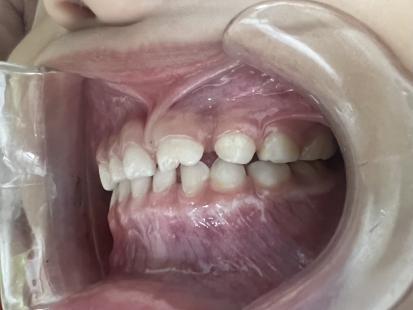

案例二:

治疗前